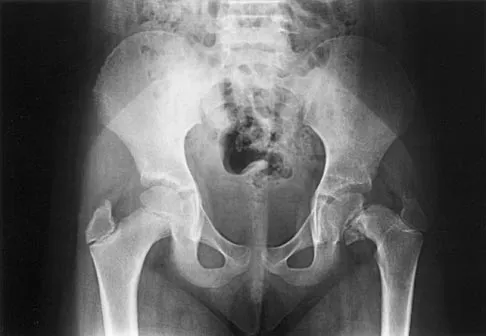

Question 19High Yield

Which of the following choices best describes the fracture pattern shown in Figures 2a through 2c?

Explanation

The fracture pattern shown in the radiographs is a fracture of the posterior column. The only line interrupted on the AP pelvis is the ilioischial line. The obturator oblique view shows that the iliopectineal line is intact as is the outline of the posterior wall. The iliac oblique view shows an interruption of the ilioischial line and an intact anterior wall. Therefore, this fracture is a fracture of the posterior column. Letournel E, Judet R: Fractures of the Acetabulum, ed 2. Berlin, Germany, Springer Verlag, 1993.